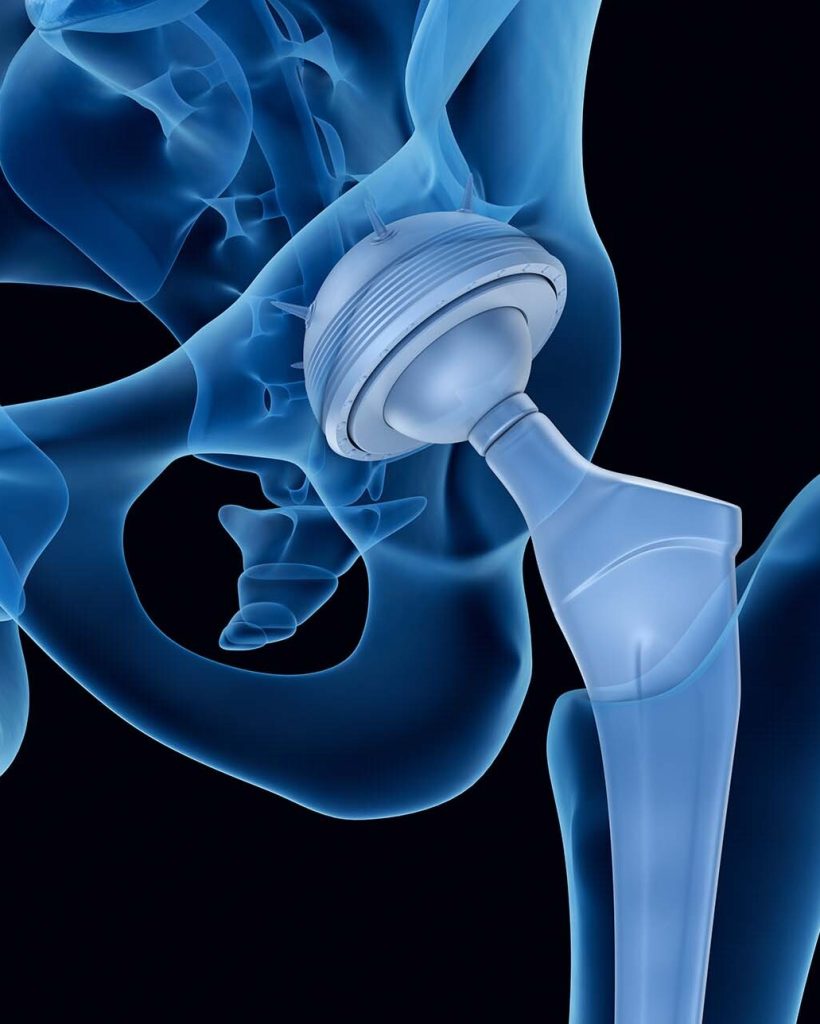

La prothèse de hanche consiste en la mise en place de composants artificiels qui reconstituent l’articulation de la hanche. Elle vise à réduire la douleur, améliorer la mobilité et augmenter la qualité de vie des patients.

Qu’est ce que la technique par voie antérieure mini invasive?

La voie antérieure pour la prothèse de hanche est une technique chirurgicale utilisée pour remplacer une articulation de la hanche. Contrairement aux approches chirurgicales traditionnelles, la voie antérieure permet d’accéder à l’articulation en passant par l’avant de la cuisse, plutôt que par l’arrière ou le côté.

Lors d’une intervention chirurgicale avec la voie antérieure, le chirurgien fait une incision sur le devant de la cuisse, généralement le long d’une ligne entre l’aine et le quadriceps. Ensuite, il sépare les muscles sans les détacher de leur insertion osseuse, ce qui permet d’éviter de couper des tendons ou des muscles importants.

Cette approche présente plusieurs avantages potentiels. Tout d’abord, elle permet une récupération plus rapide, car elle évite de couper des muscles majeurs.

Les patients peuvent souvent commencer à marcher et à se déplacer plus rapidement après la chirurgie. De plus, la voie antérieure peut réduire le risque de luxation de la prothèse de hanche, car les muscles et les tendons ne sont pas détachés ni déplacés de leur position naturelle.